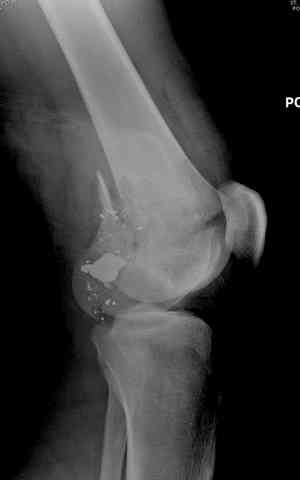

Условием для обязательного удаления пули считаем ее внутрисуставное расположение из-за возможного сатурнизма, или когда во время операции она без труда удаляется, а также поверхностно расположена.

Характерным признаком травмы с низкой кинетической энергией является отсутствие "мультифрагментации и кавитации", и поэтому в данном случае лечение можно проводить любым доступным методом.

2 внутрисуставной перелом дистального бедра с удалением пули